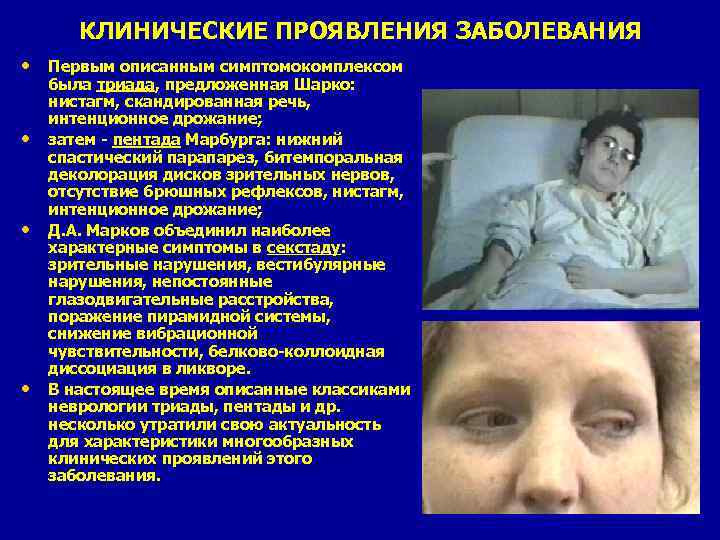

КЛИНИЧЕСКИЕ ПРОЯВЛЕНИЯ ЗАБОЛЕВАНИЯ • Первым описанным симптомокомплексом • • • была триада, предложенная Шарко: нистагм, скандированная речь, интенционное дрожание; затем - пентада Марбурга: нижний спастический парапарез, битемпоральная деколорация дисков зрительных нервов, отсутствие брюшных рефлексов, нистагм, интенционное дрожание; Д. А. Марков объединил наиболее характерные симптомы в секстаду: зрительные нарушения, вестибулярные нарушения, непостоянные глазодвигательные расстройства, поражение пирамидной системы, снижение вибрационной чувствительности, белково-коллоидная диссоциация в ликворе. В настоящее время описанные классиками неврологии триады, пентады и др. несколько утратили свою актуальность для характеристики многообразных клинических проявлений этого заболевания.